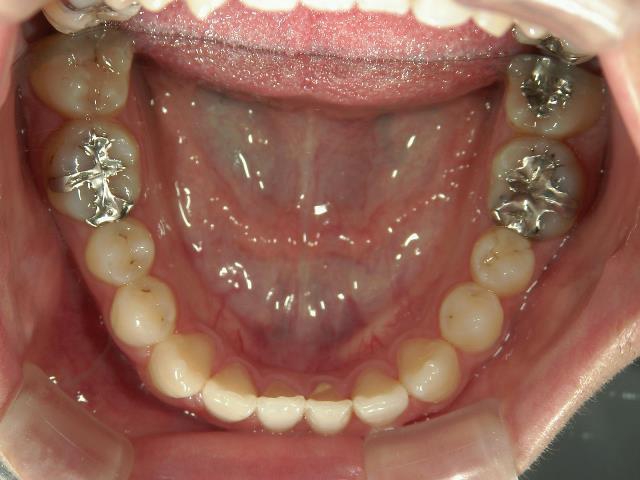

矯正歯科 治療前矯正歯科 治療前

主訴:受け口(反対咬合)を治したい

矯正歯科 治療前 急速拡大装置で上顎を広げた後、ワイヤーへ移行 非抜歯

矯正_灰色.pngno.31_7964_治療前_下.JPG矯正_灰色.png